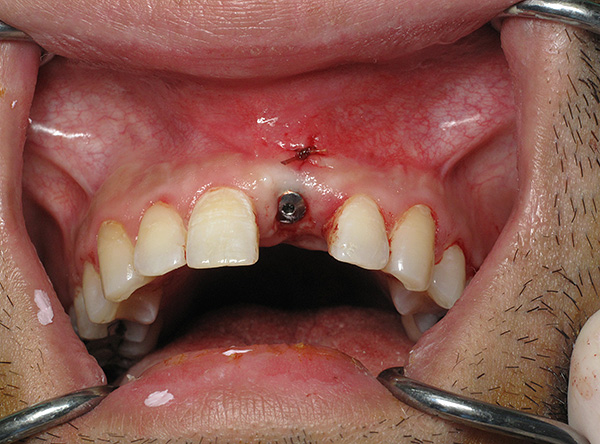

Em seguida, o retalho gengival é cortado e reclinado, um implante é inserido no orifício e o material ósseo granular é introduzido para a regeneração óssea:

Em seguida, a ponta da gengiva retorna ao seu lugar e é fixada com uma sutura: